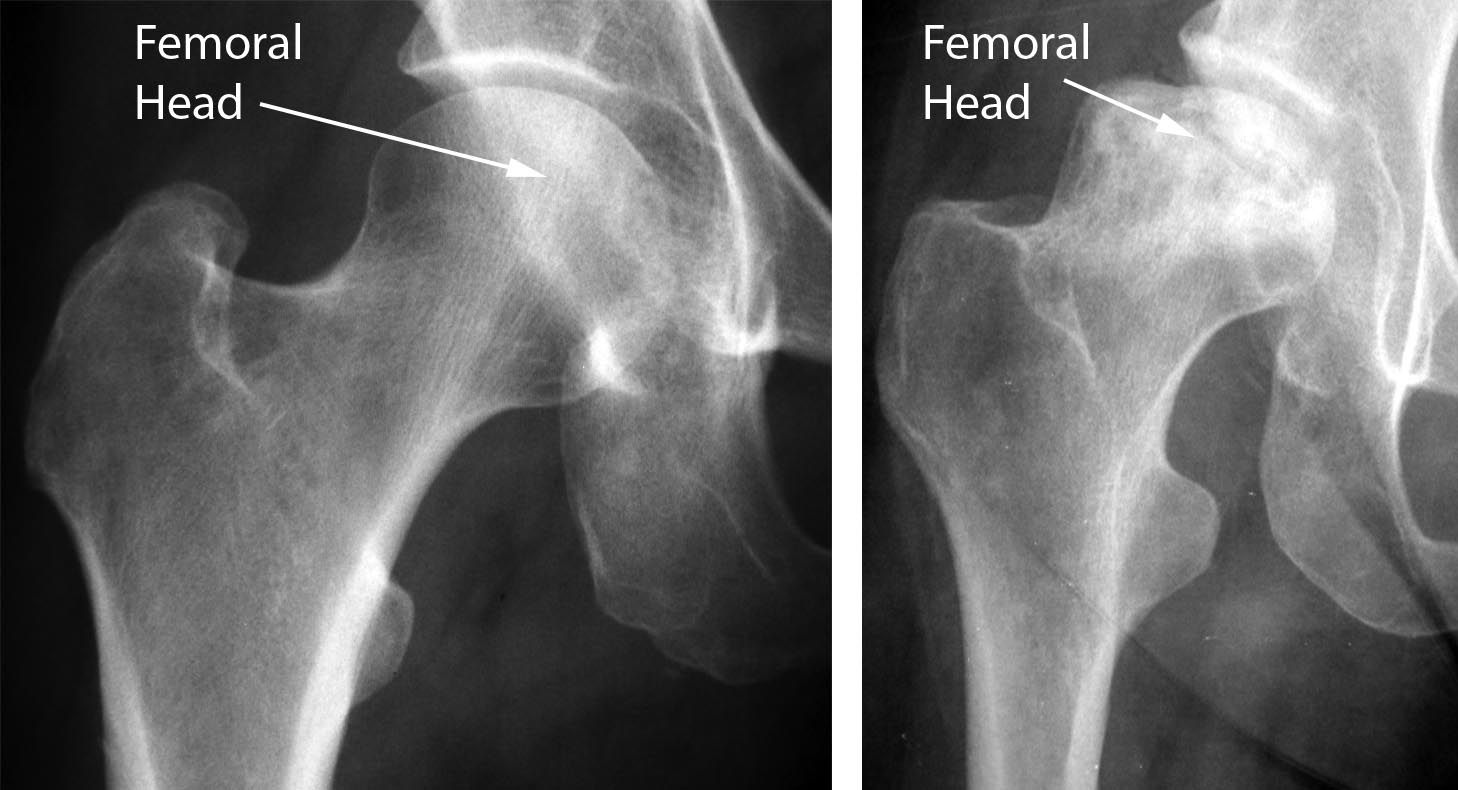

X-rays. X-rays provide images of dense structures, such as bone. X-rays are used to determine whether the bone in the femoral head has collapsed and to what degree.

Normal hip and hip with osteonecrosis

(Left) An X-ray of a healthy hip joint. (Right)  In this X-ray, the osteonecrosis has progressed to collapse of the femoral head.